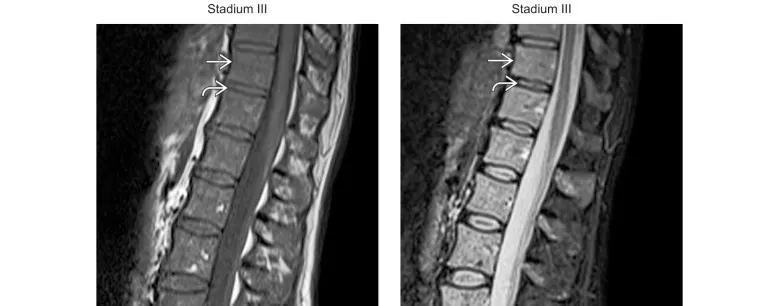

(Gauche) L’IRM T1 sagittale chez le même patient montre une diminution diffuse et sévère du signal T1 (→). Noter que ce signal T1 est inférieur à celui des disques adjacents (↱). (Droite) L’IRM STIR chez ce même patient montre un signal de STIR sévèrement augmenté de façon diffuse (→), égal à celui des disques adjacents (↱). Il s’agit du stade III, une maladie diffuse grave. Une semaine avant l’étude, une biopsie de la moelle asseuse a révelé la présence de 80 % de plasmocytes.